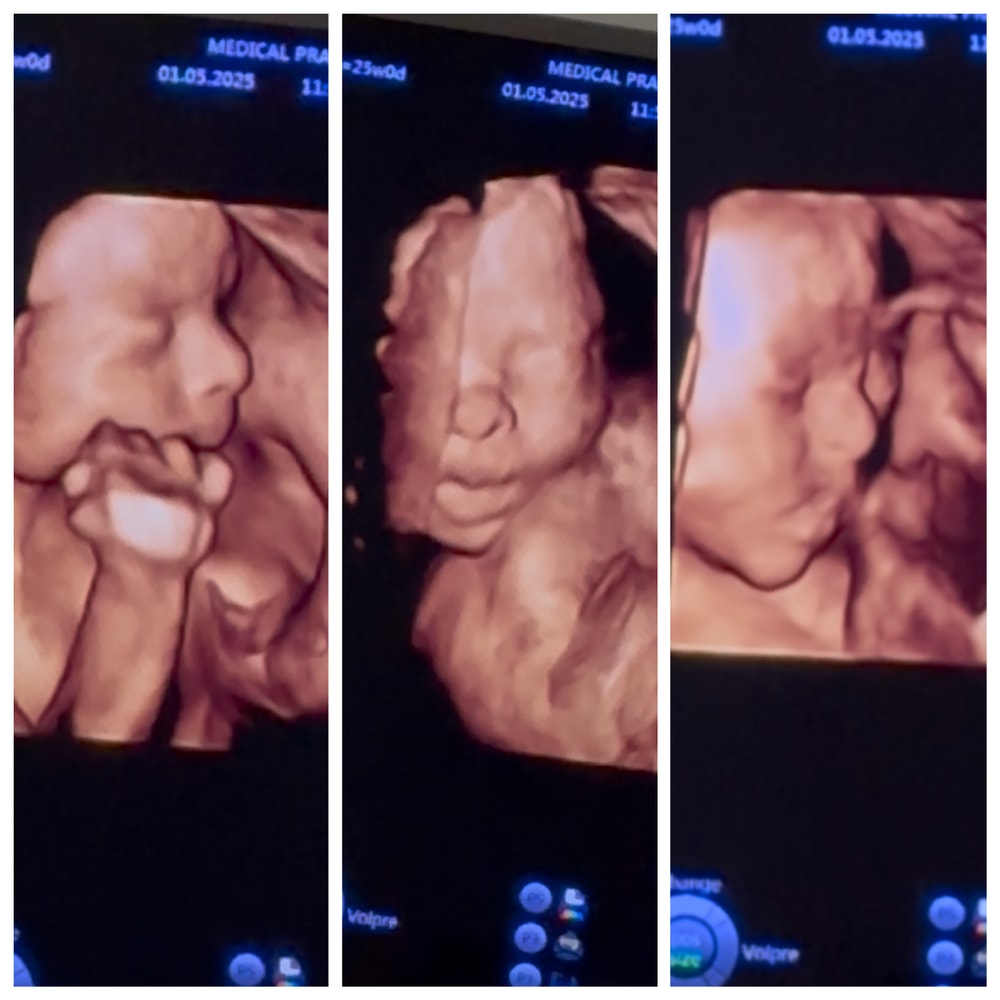

25 неделек🎀4D

Какие замечательные снимки! И новости! Ходила в 25,5 на 3D, так он закрывался, совсем чуть чуть получилось Зато есть видео, где открывает рот и сосет палец (не 3D, но хорошо различимо) Вес намерили 834гр, норма. До этого по весу отставал, очень рада, что дорос